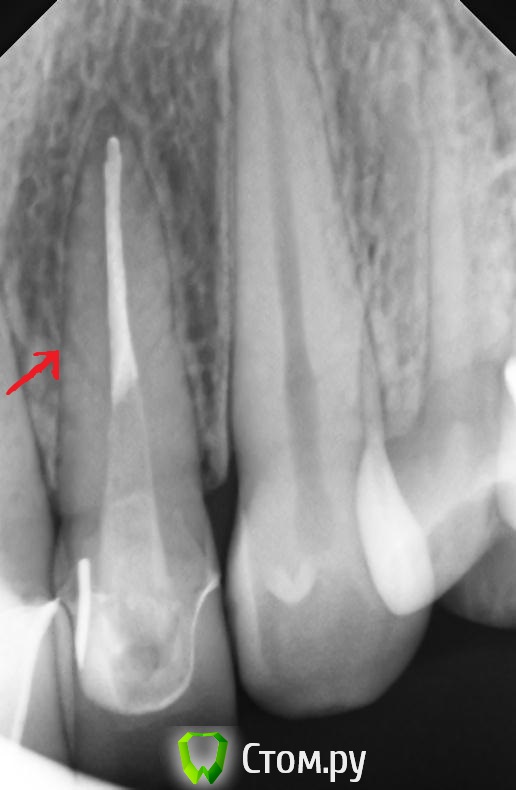

markoFFka Опубликовано 22 ноября, 2013 Поделиться Опубликовано 22 ноября, 2013 Прошу посмотреть снимок!22 зуб беспокоит после пломбирования каналов при накусывании в течение месяца.Смущают темные линии посередине корня.Не может ли это быть трещиной?или это коллатерали? вообще склоняюсь к тому,что осталось недопакована верхушка,и боли из-за этого.но все-таки смущают эти полосы посередине корня... Ссылка на комментарий

M@estro Опубликовано 22 ноября, 2013 Поделиться Опубликовано 22 ноября, 2013 Перелома нет? Есть сомнения по снимку Ссылка на комментарий

Kivilgar Опубликовано 23 ноября, 2013 Поделиться Опубликовано 23 ноября, 2013 Да,конечно пародонт)21 на снимке в девятом сообщении есть вместе с 11 и 12. 11 и 21 лечены очень много лет назад,никогда не беспокоили.отдельный снимок 11 и 12 делали летом,сейчас не могу выложить.в данном случае точно не они.Перкуссия положительна именно 22го.Тогда только и остается http://s57.radikal.ru/i156/1311/fd/209d7896d0be.jpg 6 Ссылка на комментарий

Scrabble Опубликовано 24 ноября, 2013 Поделиться Опубликовано 24 ноября, 2013 (изменено) СВШ установлен не по протоколу: надо бы за 3-4 мм до верхушки. Хотя по статистике, которую приводил Соломонов на лекции "Endoprostodontic relationship" переломы с СВШ встречаются крайне редко. Просто при таком позиционировании штифта, как в вашем случае, реставрация на СВШ получается подвижной при латеральных нагрузках-что, собственно, может быть причиной болей. Изменено 24 ноября, 2013 пользователем Scrabble 1 Ссылка на комментарий

zubkindoctor Опубликовано 26 ноября, 2013 Поделиться Опубликовано 26 ноября, 2013 СВШ установлен не по протоколу: надо бы за 3-4 мм до верхушки. Хотя по статистике, которую приводил Соломонов на лекции "Endoprostodontic relationship" переломы с СВШ встречаются крайне редко. Просто при таком позиционировании штифта, как в вашем случае, реставрация на СВШ получается подвижной при латеральных нагрузках-что, собственно, может быть причиной болей.верно мыслите,но думаю мало времени прошло еще.СВШ в пределах кости-уже хоть что-то.ЭТо не оправдывает длину СВШ,но циклических нагрузок за 3 недели было недостаточно, что бы вызвать перелом корня(если пациент,конечно, не штангист, "Бруксист", и т .д )Хотя...Если там и есть трещина,то скоро это будет видно) Ссылка на комментарий

Scrabble Опубликовано 26 ноября, 2013 Поделиться Опубликовано 26 ноября, 2013 верно мыслите,но думаю мало времени прошло еще.СВШ в пределах кости-уже хоть что-то .ЭТо не оправдывает длину СВШ,но циклических нагрузок за 3 недели было недостаточно, что бы вызвать перелом корня(если пациент,конечно, не штангист, "Бруксист", и т .д )Хотя...Если там и есть трещина,то скоро это будет видно )Я как раз не про перелом, а про "болтание и прокручивание" реставрации с опорой на штифт, позиционированный данным образом. Ссылка на комментарий